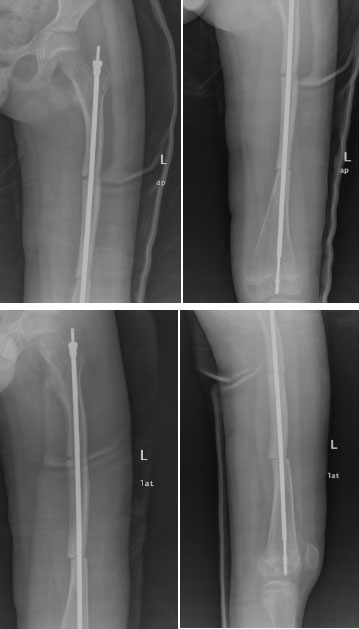

面對(duì)成骨不全的特殊病例,小兒骨科采用目前最先進(jìn)、最可靠的手術(shù)方式,選擇左股骨骨折切開復(fù)位、左股骨弓形變截骨矯形可延長(zhǎng)髓內(nèi)釘內(nèi)固定術(shù)。在小兒骨科及麻醉科的共同配合下,手術(shù)歷經(jīng)2.5小時(shí),圓滿順利完成。

圖為患者股骨弓形變截骨矯形可延長(zhǎng)釘內(nèi)固定術(shù)后影像學(xué)資料